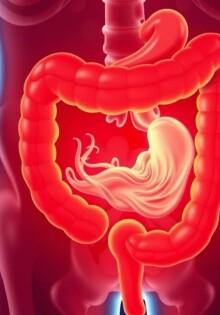

Dolor abdominal derecho: posibles diagnósticos alternativos que debes conocer

Apendicitis y gastroenteritis: cómo diferenciarlas

Diferencia entre apendicitis y diverticulitis: cómo reconocer, diagnosticar y tratar dos causas comunes de dolor abdominal